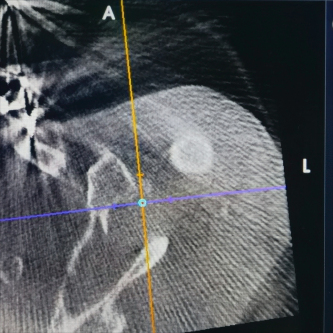

(术前X线及CT片)

患者因交通事故致伤导致左肩关节盂骨折及左肩锁关节脱位和右尺桡骨骨折,骨折移位明显,疼痛剧烈,具备手术指征。但患者为75岁高龄,基础疾病多,担心患者无法耐受过大的手术创伤。经术前讨论,创伤外科中心张立峰教授团队决定为患者应用骨科手术机器人辅助经皮内固定治疗肩关节盂骨折的手术方案。术中,通过机器人进行采集数据、并规划手术等人工智能操作,仅用1cm切口即成功完成手术。